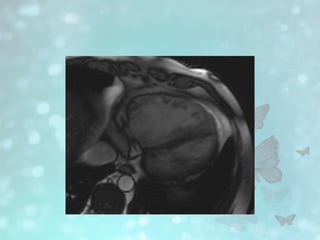

• #17 True fast imaging with steady-state precession image shows aneurysm formation of right ventricular wall (arrow)

• #18 . True fast imaging with steady-state precession image in systole shows marked dilatation of right ventricle. These findings satisfy two major diagnostic criteria for arrhythmogenic right ventricular cardiomyopathy